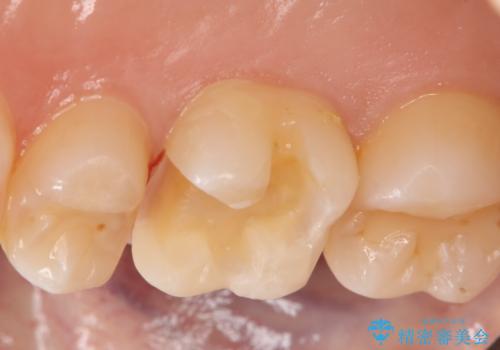

- 右上6番の虫歯治療を主訴に来院された患者様です。

切削量・形態を考慮し、セラミックインレーでの治療を計画しました。

保険の材料が劣化し中で虫歯が進行していたので、全て取り除いた上で形を整え型をとりインレーをセットしています。